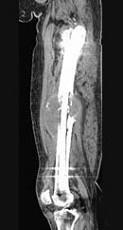

问题 男,18岁,右股骨肿瘤术后,现大腿中部疼痛、肿胀,夜间尤甚,结合CT图像,最可能的诊断是 ( )

选项 A、成骨性骨转移瘤 B、化脓性骨髓炎 C、Ewing肉瘤 D、骨肉瘤 E、骨纤维肉瘤

答案 D